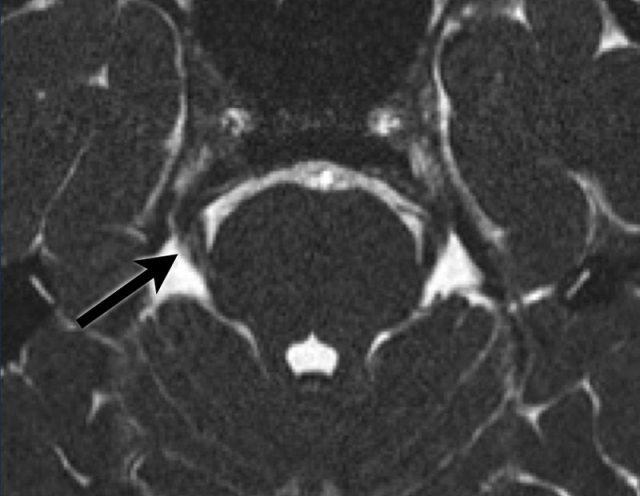

Hình ảnh này của bệnh nhân nam 26 tuổi có biểu hiện giảm cảm giác vùng mặt bên phải tiến triển chậm.

Hình ảnh chuỗi xung T2W theo mặt phẳng axial cho thấy một tổn thương tăng tín hiệu tại nhân dây thần kinh sinh ba (mũi tên).

Đây có thể là dấu hiệu của tình trạng mất myelin, chẳng hạn như trong bệnh xơ cứng rải rác.